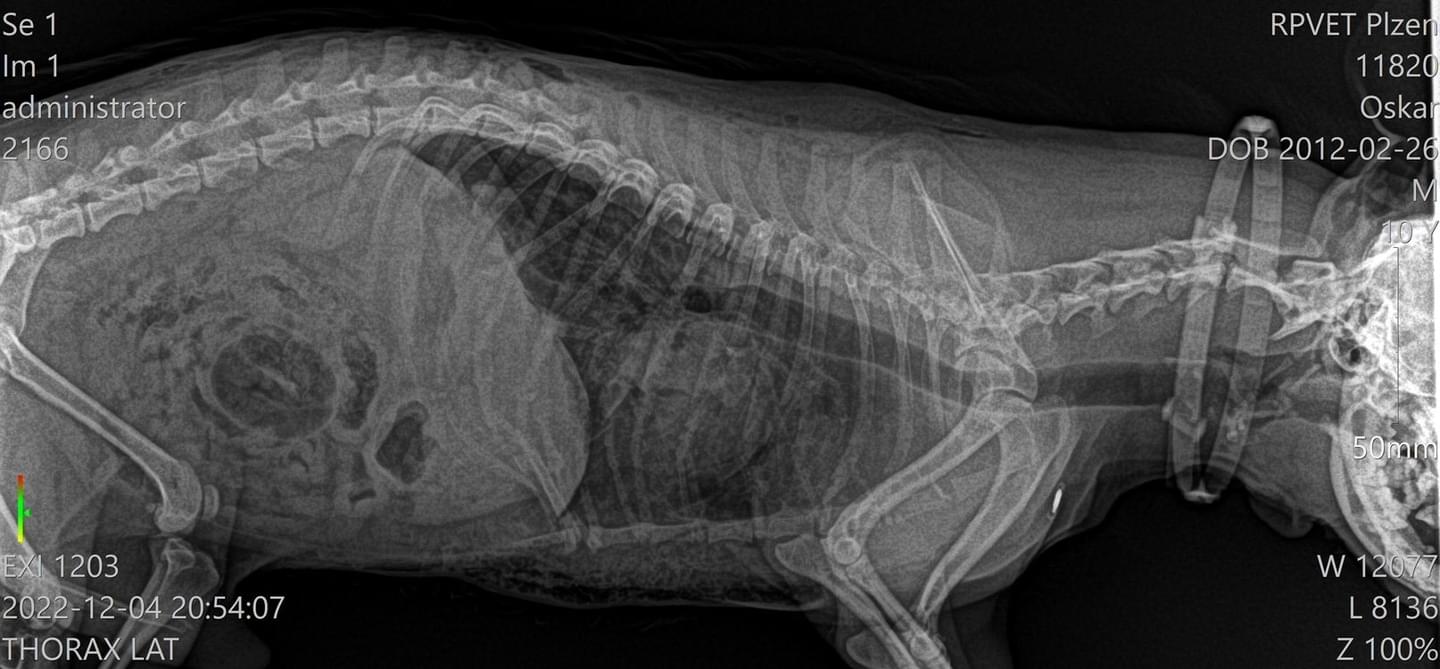

"Oskar ležel na zemi v krvi, takže jsme ho sebrali a hned jeli na veterinární pohotovost. Tam mu udělali RTG a jiná vyšetření, načež nám řekli, že má polámaná žebra a pneumothorax. Bylo nám oznámeno, že pokud přežije noc, udělá se chirurgický zákrok, ale po deseti minutách zemřel na kardiopulmonární selhání."